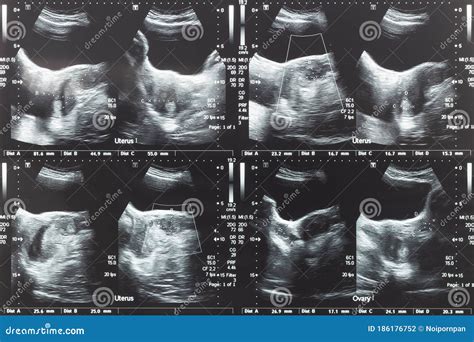

Diagnosing issues related to the lower abdomen of women often involves a combination of medical history, physical examination, and diagnostic tests. Some common diagnostic methods include:

• Ultrasound: An imaging test that uses sound waves to create pictures of the internal organs.